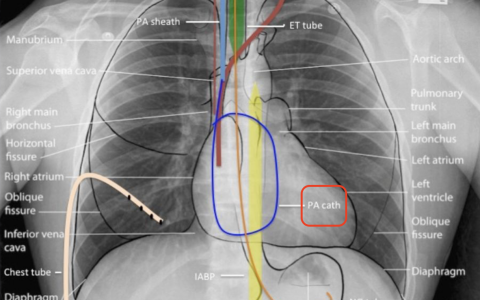

主动脉内球囊反搏

Swan-Ganz漂浮导管